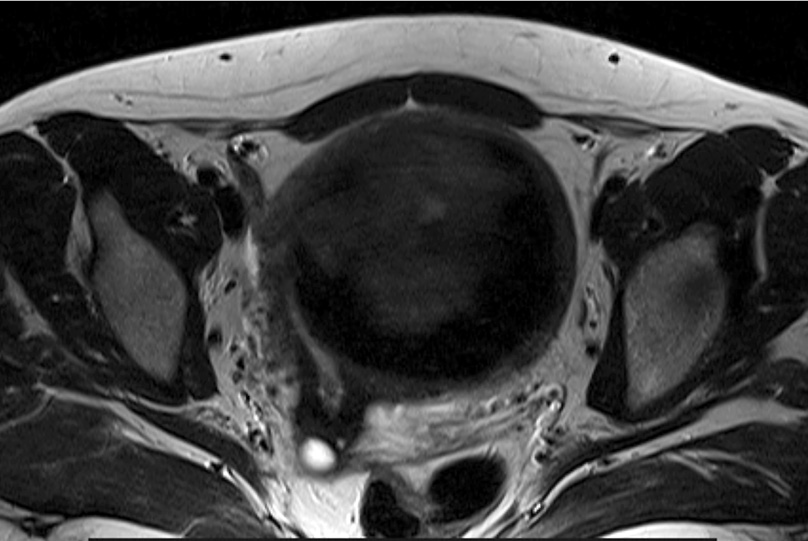

При поступлении пациентке проведено МРТ органов малого таза с контрастированием (рис. 7): матка увеличена до 122×98×107 мм за счет массивного шаровидного миоматозного узла по передней стенке до 89 мм в диаметре. Правый яичник расположен над маткой, общим размером 24×14×30 мм, его структура гомогенная, фолликулярный аппарат выражен слабо, с наличием немногочисленных мелкокистозных включений до 5 мм в диаметре. Левый яичник расположен в задних отделах таза над маткой, общим размером 23×19×28 мм, фолликулярный аппарат выражен слабо, с наличием немногочисленных мелкокистозных включений до 5 мм в диаметре. При оценке DWI/ADC – без особенностей.

Рис. 7. Клинический пример №2. МРТ с контрастированием до проведения ЭМА. / Fig. 7. Clinical case 2. Contrast-enhanced MRI before UAE.